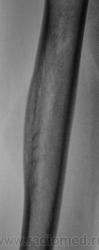

Пациентка направлена врачом хирургом на рентгенографию правой плечевой кости. Пациентка жалуется на боли в плече, как дневные, так и ночные, отмечает, что эти боли усиливаются при физической нагрузке. Из "разговора" выяснено, что боли резко усилились в течение последних двух месяцев. Пациентка отмечает, что боли усиливаются при физической нагрузке. Выяснено, что 1,5 года тому был удар (упала), в то место, которое болит. Что посоветуете, уважаемые коллеги?

Хоть убей, ничего плохого не вижу. Дельт. бугристость, как бугристость. Разве что-то выше - то ли деструкция с секвестром? Напишем кортикалит!

А что это за поперечные линии - костной перестройки, что ли?

Изображения в прямой проекции с увеличением.

На снимках справа латерально вроде как прослеживается "мягкотканный компонент". На левой такого нет. А может просто справа мышцы плотнее и накладываются друг на друга, т.к правша?

Мне кажется, есть локальная слоистость кортикального слоя. Надо бы спросить ту, имя которой я поклялся не упоминать.